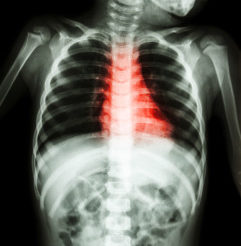

What is COPD? It stands for chronic obstructive pulmonary disease, and it typically describes two…